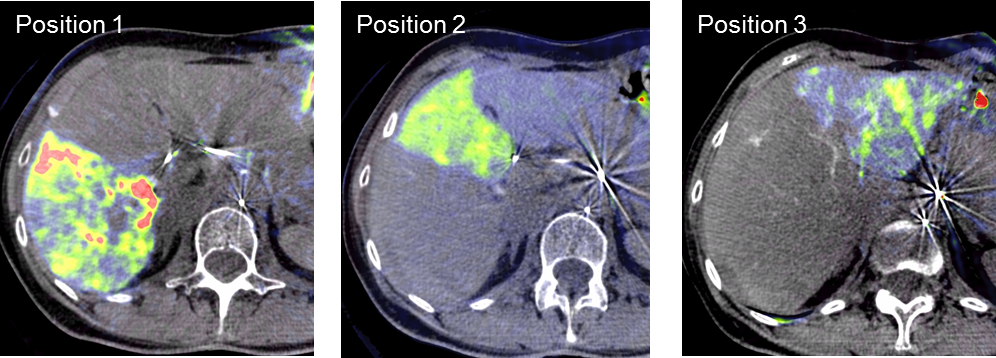

Die Selektive Interne Radiotherapie (SIRT) wird in der Fachliteratur auch Radioembolisation (RE) genannt. Hierbei werden gezielt kleine, radioaktive Kügelchen, sog. Mikrosphären, über den Katheter (siehe TACE) von mehreren Positionen in der Leber mit dem Blutstrom in das gut durchblutete Tumorgewebe gebracht und bleiben dort in den kleinen Gefäßen "stecken", die den Tumor ernähren. Von dort bestrahlt das in den Kügelchen enthaltene radioaktive Element Yttrium-90 über mehrere Tage hinweg das Tumorgewebe und zerstört es selektiv. Dieses Verfahren kann bei Leberkrebs oder -metastasen eingesetzt werden, wenn die Herde trotz Chemotherapie weiter wachsen und nicht chirurgisch oder mittels RFA und TACE behandelbar sind.

Das Verfahren wird von der interventionellen Radiologie zusammen mit der Partnerabteilung der Nuklearmedizin sowie den entsprechenden Partnerkliniken geplant und durchgeführt.